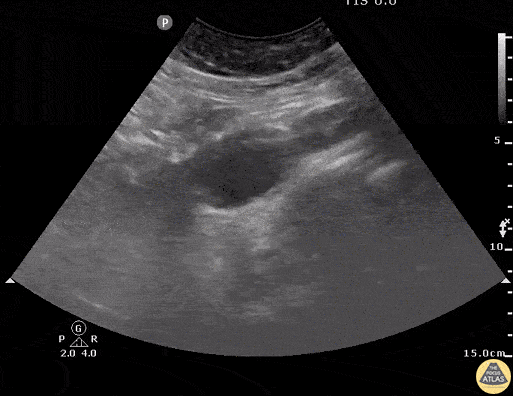

Aorta - Dissection Flap in Abdominal Aorta

An elderly male with hypertension and DM presents with C/O chest pain. Bedside ultrasound performed demonstrating a dissection flap in the lumen of the abdominal aorta. A subsequent parasternal long axis show extension into descending thoracic aorta as well. Image courtesy of Robert Jones DO, FACEP @RJonesSonoEM Director, Emergency Ultrasound; MetroHealth Medical Center; Professor, Case Western Reserve Medical School, Cleveland, OH View his original post here.